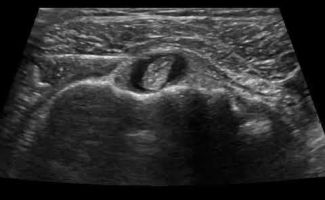

- Έγχυση Kορτικοστεροειδούς στο περίβλημα (έλυτρο) του τένοντα: Η έγχυση με κορτιζόνη καταστέλλει τη φλεγμονή γύρω από τον τένοντα, οδηγώντας στην άμεση ανακούφιση του ασθενούς από το πόνο και το πρήξιμο. Η στοχευμένη διενέργεια αυτών των ενέσεων είναι πολύ σημαντική: η έγχυση πρέπει να γίνει στο περίβλημα του τένοντα, και όχι στο εσωτερικό του, καθώς η έγχυση στο εσωτερικό μπορεί να προκαλέσει φθορά και ρήξη του τένοντα. Τα μηχανήματα υπερήχων μας παρέχουν το απαραίτητο επίπεδο ακρίβειας καθώς καθοδηγούμε τη βελόνα με ταυτόχρονη απεικόνιση και διοχετεύουμε το φάρμακο εκεί ακριβώς που χρειάζεται. Επομένως, το επίπεδο ακρίβειας που εγγυάται η απεικόνιση σημαίνει ότι υπάρχει υψηλή πιθανότητα η θεραπεία να είναι ακόμα πιο αποτελεσματική.

- Απόλυτη Ακρίβεια: Οι υπέρηχοι επιτρέπουν στους Ιατρούς-Ακτινολόγους να εντοπίζουν με ακρίβεια τον φλεγμονώδη τένοντα και να οπτικοποιούν τη θέση της βελόνας κατά τη διάρκεια της ενέσεως. Αυτή η στοχευμένη προσέγγιση εξασφαλίζει την τοποθέτηση της ένεσης με ακρίβεια στην περιοχή που πλήττεται, βελτιώνοντας την αποτελεσματικότητά της.

- Ασφαλείς: Σε σύγκριση με την ενέσιμη θεραπεία χωρίς υπερηχογραφική καθοδήγηση (τυφλή ένεση), η εικόνα πραγματικού χρόνου επιτρέπει στον ιατρό να διεξάγει την ένεση ακριβώς στο σημείο που χρειάζεται, αποφεύγοντας επικίνδυνες περιοχές όπως τα νεύρα και τα αγγεία.